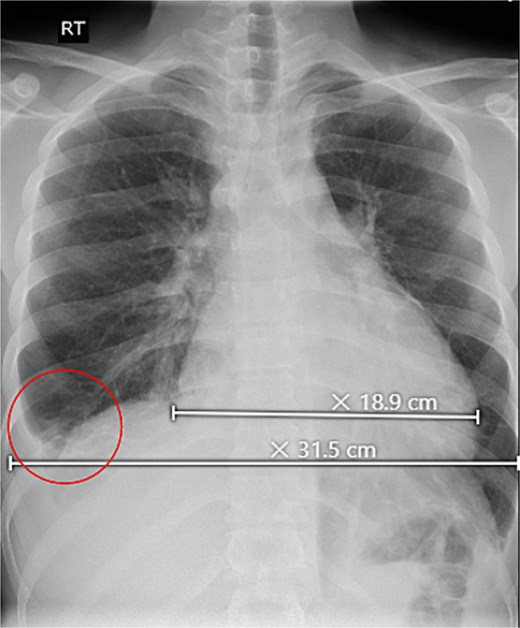

Initial investigations revealed abnormal liver enzymes and elevated inflammatory markers (Table 1). A chest X-ray showed a minimal right-sided pleural effusion and an increased heart-to-chest ratio (Fig. 1). Abdominal ultrasound showed an enlarged liver measuring 18.2 cm, an irregular liver capsule, a mildly dilated portal vein of 1.4 cm, and fluid in the abdominal cavity, suggesting liver congestion. Analysis of the abdominal fluid showed a serum-to-ascitic albumin gradient >1.1, indicating a fluid buildup due to increased pressure in the blood vessels of the liver (Table 2).

Upright chest X-ray, revealed an increase in cardiothoracic ratio with a minimal right-sided pleural effusion (circle).